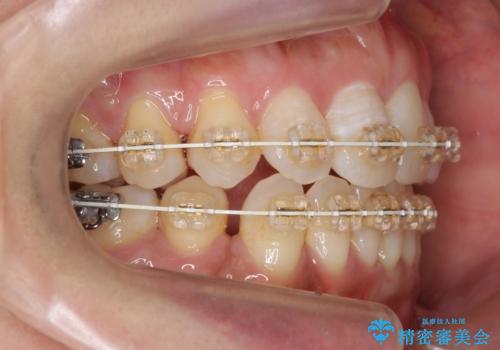

- 矯正装置

- 審美装置

- 前歯の重なりを主訴に来院。

前歯が顔の真ん中に飛び出しているような状態でした。

右上の犬歯が奥深く埋伏していました。

右上以外の3本を抜歯しきちんと並べました。

成人の矯正でしたので、矯正治療前にしっかり必要な歯周病治療を行い、状態が改善してから開始しました。

前歯も引っ込み、口が閉じやすくなりました。